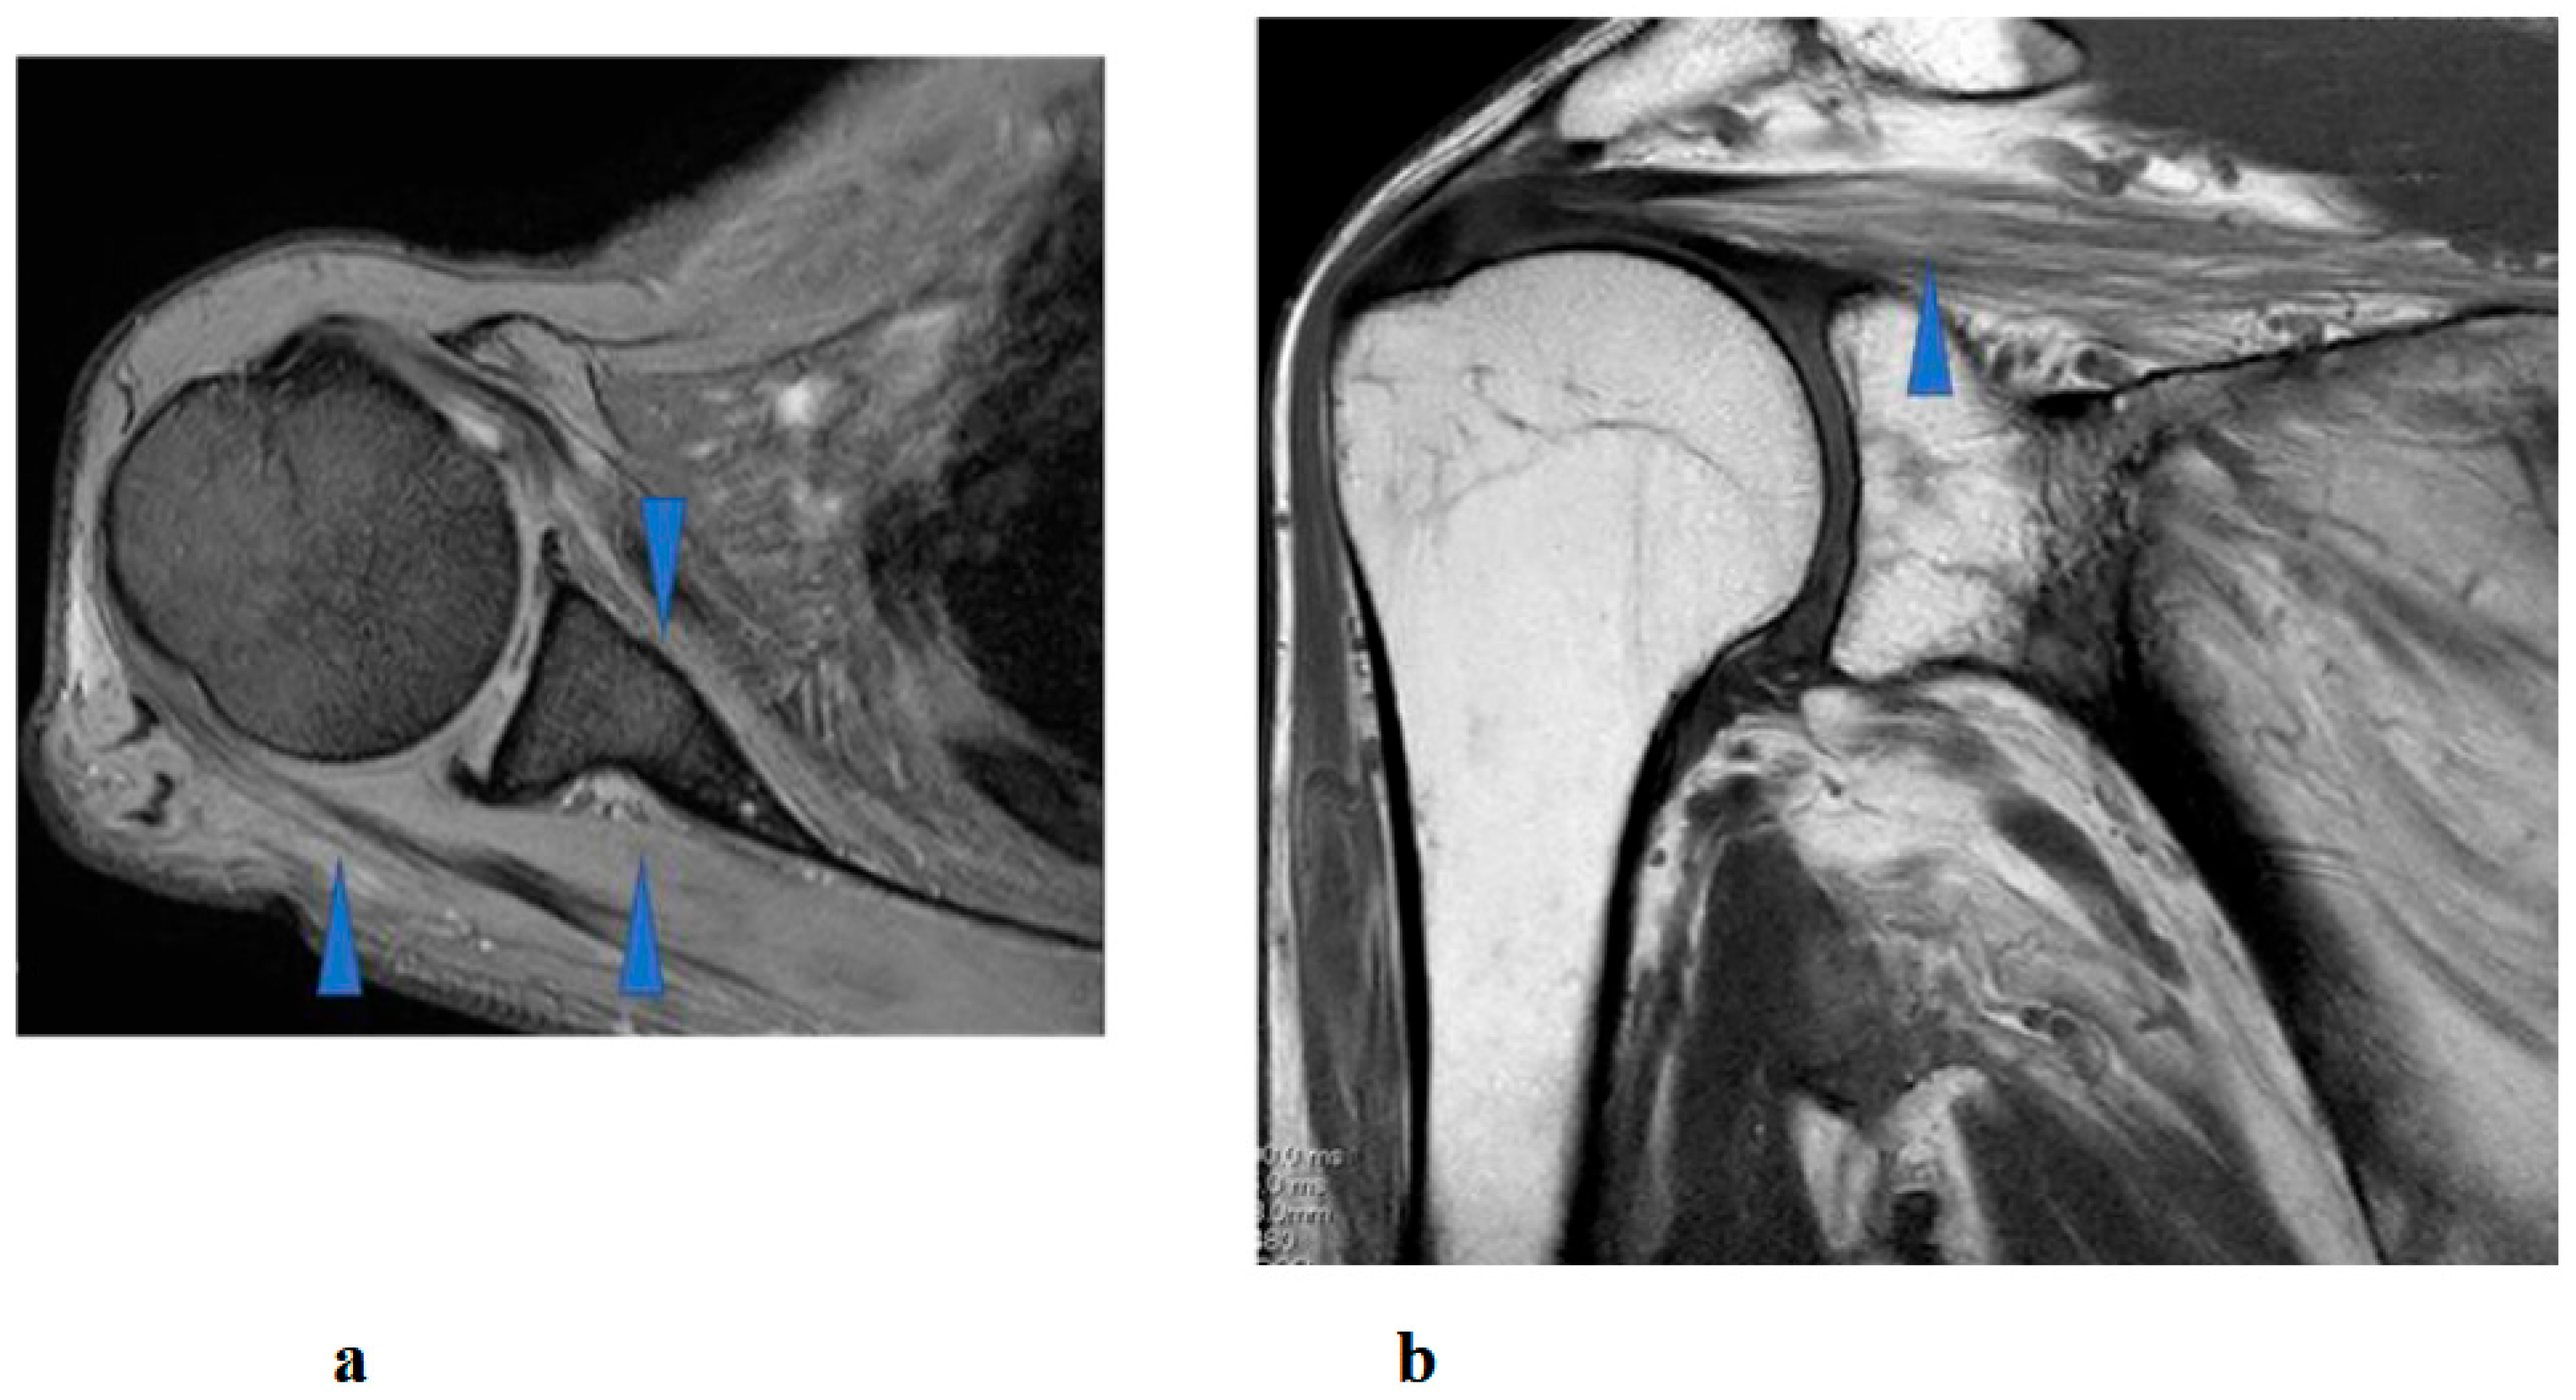

Right shoulder T1- and T2-weighted MRI before intervention showed atrophy and fatty infiltration of several musculus, including supraspinatus, deltoideus, and subscapularis on sagittal and coronal. Following 8 months and 14 months started HAL training. MRI showed no change in atrophy and fatty infiltration of the supraspinatus, deltoideus, and subscapularis. This assessment was backed by a radiologist (Figure 8).

Figure 8.

Right shoulder T1 and T2-weighted magnetic resonance imaging showed atrophy and fatty infiltration of several musculus, including supraspinatus, deltoideus, and subscapularis (arrow) on coronal (a) and sagittal (b).

Interestingly, despite the patient’s functional improvements in ROM and muscle strength, serial MRI assessments performed at 8 and 14 months after the initiation of HAL therapy demonstrated no appreciable reversal of atrophy or fatty infiltration in the supraspinatus, deltoid, or subscapularis muscles. This finding suggests that the observed recovery was not primarily attributable to structural restoration of muscle bulk, but rather to neuromuscular mechanisms such as enhanced recruitment of residual motor units, cortical reorganization, and motor learning facilitated by interactive biofeedback training with HAL [18]. In cases of chronic peripheral neuropathy with longstanding muscle weakness (MMT grade 2 persisting for years), spontaneous recovery is generally considered limited. Therefore, the improvement observed in this patient may have resulted from hypertrophy of partially innervated muscle fibers, increased efficiency of motor unit recruitment, and central neuroplastic adaptations compensating for peripheral denervation [19]. Moreover, by providing real-time biofeedback and suppressing maladaptive compensatory patterns, HAL therapy may have facilitated more physiologic movement strategies, thereby amplifying the functional gains.